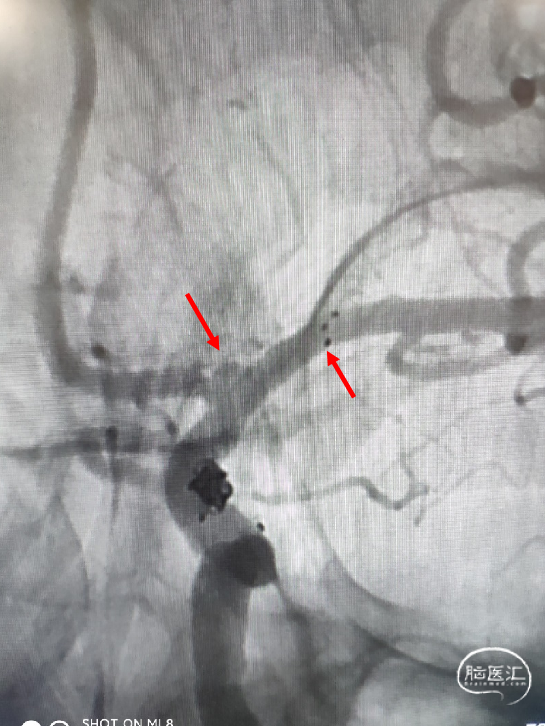

患者一期治疗使用Neuroform EZ支架重塑右侧大脑中M1狭窄段,但支架远端定位落于中干,紧邻动脉瘤开口处,故封堵动脉瘤瘤颈的支架只能穿过第一枚支架的网孔释放于下干支。

为充分保护分支血管使手术顺利进行,拟释放一枚LEO+Baby支架于下干支,与Neuroform EZ支架形成“T型”,既能很好地保护瘤颈,也能避免做“Y型”时支架交叉及重叠区域打开不良。

2. 穿Neuroform EZ支架网孔,将支架微导管及弹簧圈微导管分别超选到位。

3. 支架平行全释放后填圈。

支架微导管到位后,释放支架。

支架释放后,送入首枚2*4的弹簧圈栓塞动脉瘤。

送入第二枚1.5*2的弹簧圈致密栓塞动脉瘤。

术后造影显示动脉瘤致密栓塞,不再显影;其它各分支血管通畅。

术后造影模拟血管重建显示支架头端完全覆盖动脉瘤瘤颈,并且与一期释放的支架远端形成“Kissing”。